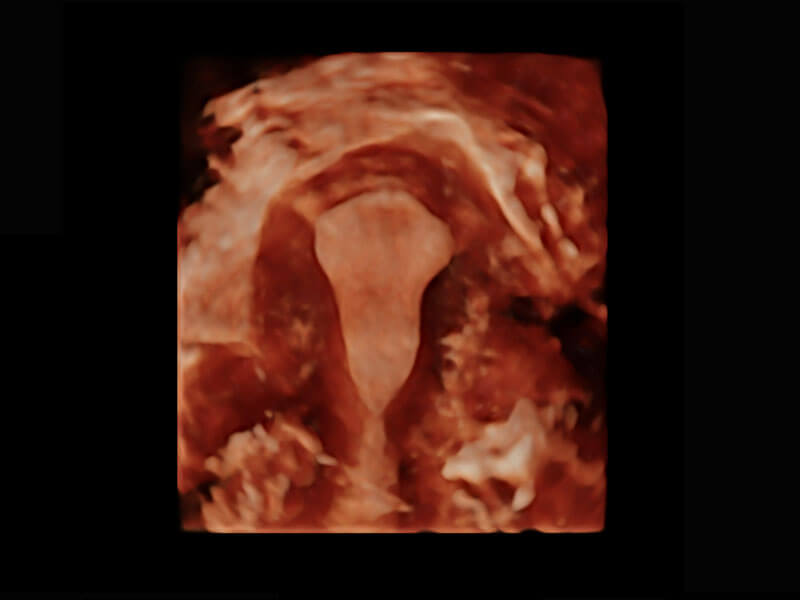

P60搭载一系列胎儿心脏成像技术,实现精细的胎儿心脏评估。

右室双出口

胎心容积成像